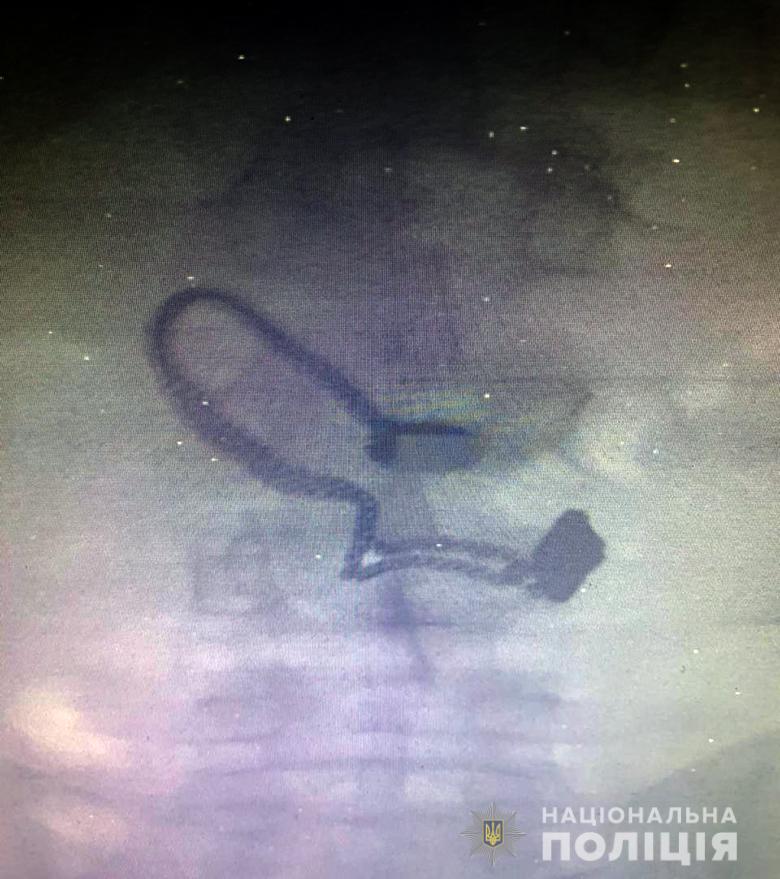

В Киеве задержанный грабитель проглотил сорванную с шеи женщины цепочку

Грабителем оказался 26-летний житель Луганской области, ранее уже судимый за кражи. Его задержали. Во время поверхностного осмотра у мужчины нашли кошелек потерпевшей. Позже он признался полицейским, что сорванную цепочку проглотил.

"Во время медосмотра на рентген-снимке задержанного врачи обнаружили украшение", - сообщают в полиции.